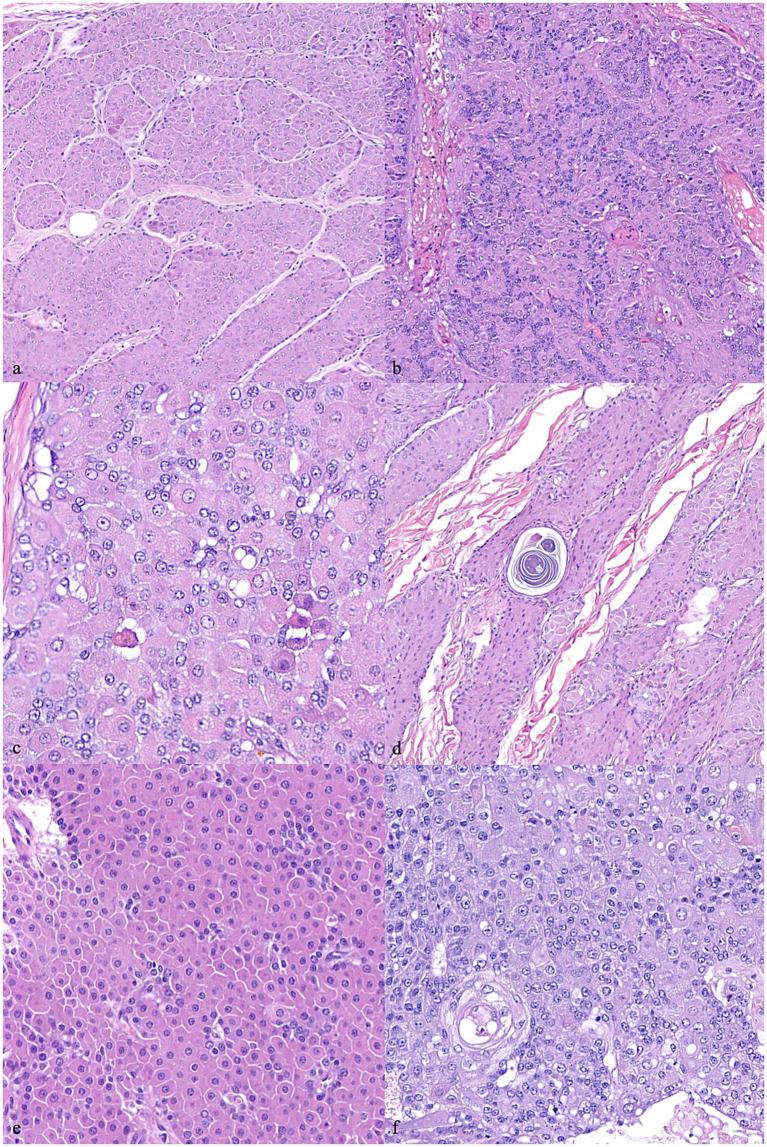

Hepatoid perianal gland tumors are relatively common in dogs, accounting for 25% of all skin tumors. However, the specific factors involved in their development are still not completely clear. It has been established that hormonal influences can impact the formation of these tumors. The prognosis for dogs with perianal tumors depends largely on histology (benign vs. malignant) and, in case of malignancy, it has been suggested that the stage of the disease is important, with a more favorable outcome in dogs having small (under 5 cm in diameter), -metastatic adenocarcinomas which are surgically removed with non-infiltrated margins. Nevertheless, there is a paucity of studies which thoroughly relate hepatoid gland histotypes to their prognosis; therefore, it is possible that a well-differentiated adenocarcinoma could be misclassified. Based on a retrospective review of 76 dogs with hepatoid gland tumors having clinical follow-up, the aims of this study were (1) to establish a histological grading system capable of potentially predicting prognosis and (2) to explore the role of Ki67 as a potential prognostic marker. Based on histopathological features only, the proposed grading system effectively differentiated tumors with a favorable prognosis from those with a worse prognosis to support histological diagnosis. The evaluation of the Ki67 index was not useful to predict prognosis in this study.

类肝癌性肛周腺肿瘤在犬类中相对常见,占所有皮肤肿瘤的25%。然而,其发生发展所涉及的具体因素仍不完全清楚。已经确定激素影响会对这些肿瘤的形成产生作用。患有肛周肿瘤的犬类的预后很大程度上取决于组织学类型(良性与恶性),对于恶性肿瘤而言,疾病分期很重要,直径小于5厘米、无转移的腺癌且手术切除边缘未受浸润的犬类预后较好。然而,将类肝癌组织学类型与其预后进行全面关联的研究较少;因此,高分化腺癌可能会被错误分类。基于对76只患有类肝癌肿瘤且有临床随访记录的犬类进行的回顾性研究,本研究的目的是:(1)建立一个能够潜在预测预后的组织学分级系统;(2)探索Ki67作为潜在预后标志物的作用。仅基于组织病理学特征,所提出的分级系统有效地将预后良好的肿瘤与预后较差的肿瘤区分开来,以支持组织学诊断。在本研究中,Ki67指数的评估对预测预后并无帮助。